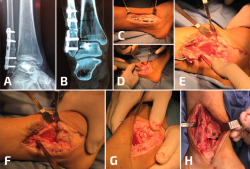

Durante la reconstrucción de la pseudoartrosis, es esencial realizar una artrotomía anterolateral para visualizar la reducción anatómica del peroné (Figura 1); sin embargo, el desbridamiento artroscópico de la articulación debe realizarse en forma simultánea no tanto para determinar el grado de artritis del tobillo, sino para tratar alguna lesión osteocondral no visible con la artrotomía anterolateral.

Figura 1. Cuando es necesaria una elongación significativa, se debe desbridar toda la sindesmosis anterior y dejar libre el peroné. Es indispensable para este paso un separador de láminas.

El tejido hipertrófico entre el maléolo interno y el astrágalo debe resecarse desde el receso interno para el correcto reposicionamiento del astrágalo. Esto se puede lograr por vía artroscópica o mediante una artrotomía anteromedial. Esto es importante tenerlo en cuenta, ya que una pequeña cantidad de tejido en la gotera interna puede bloquear el correcto desplazamiento medial del astrágalo dentro de la mortaja. La pseudoartrosis del peroné por lo general se asocia con un desplazamiento lateral del astrágalo, con un aumento del espacio claro medial, motivo por el cual se debe limpiar toda la gotera interna (Figura 2).

Figura 2. Aquí mostramos la técnica de elongación. Después del desbridamiento de la sindesmosis, se coloca la placa sobre el peroné y de colocan 2 o 3 tornillos distales (A, B). Se coloca un tornillo de 3,5 en el peroné proximal a la placa y el separador de láminas entre el tornillo y el borde proximal de la placa (C, D). En este caso, para corregir la consolidación viciosa del maléolo medial, se realizó una osteotomía (E) y el control de radioscopia intraoperatorio muestra una buena reducción de la sindesmosis (F).

La artrotomía interna se realiza mediante una incisión de 2 cm medial al tendón tibial anterior directamente sobre la gotera interna. La incisión se profundiza hasta llegar a la articulación, para luego resecarse el tejido sinovítico hipertrófico, la cápsula y el tejido fibrótico que se encuentra en la gotera interna.

Resulta de gran utilidad la utilización de una gubia, que se debe girar 180° para garantizar que el receso interno quede totalmente libre y que el astrágalo esté móvil. Posterior a esto, se intenta llevar el astrágalo a medial, para corroborar que la gotera se encuentre limpia por completo y poder trabajar posteriormente con tranquilidad en la corrección de la pseudoartrosis del peroné.